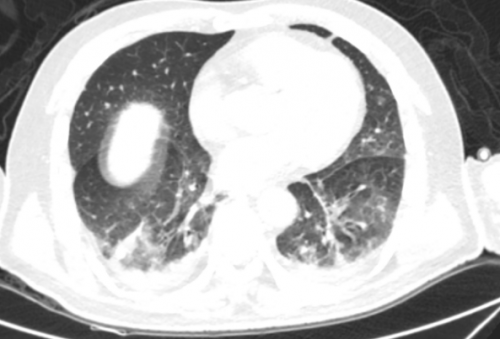

11月30日肺部CT

两肺渗出性改变,较前片两肺渗出、实变有吸收。